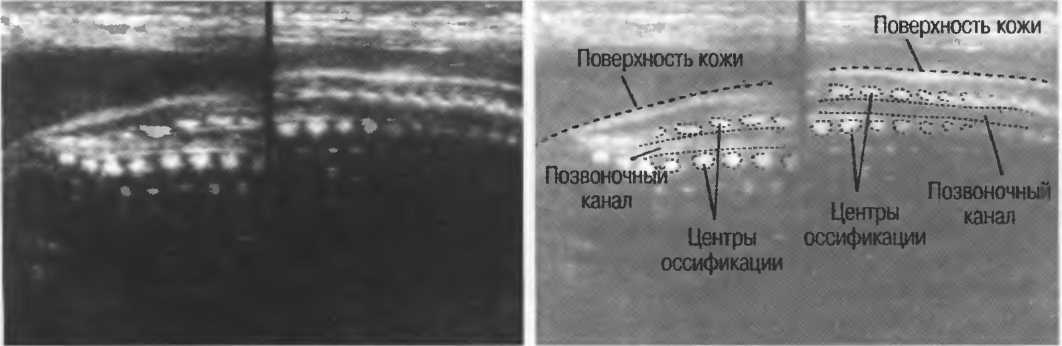

Рис.5. Два поперечных среза плода, демонстрирующих тень от позвоночника плода. Аналогичная тень от ребер может частично закрывать почки или печень. Изменяя угол наклона датчика, можно изменить положение тени таким образом, чтобы подлежащие ткани были видны отчетливо.